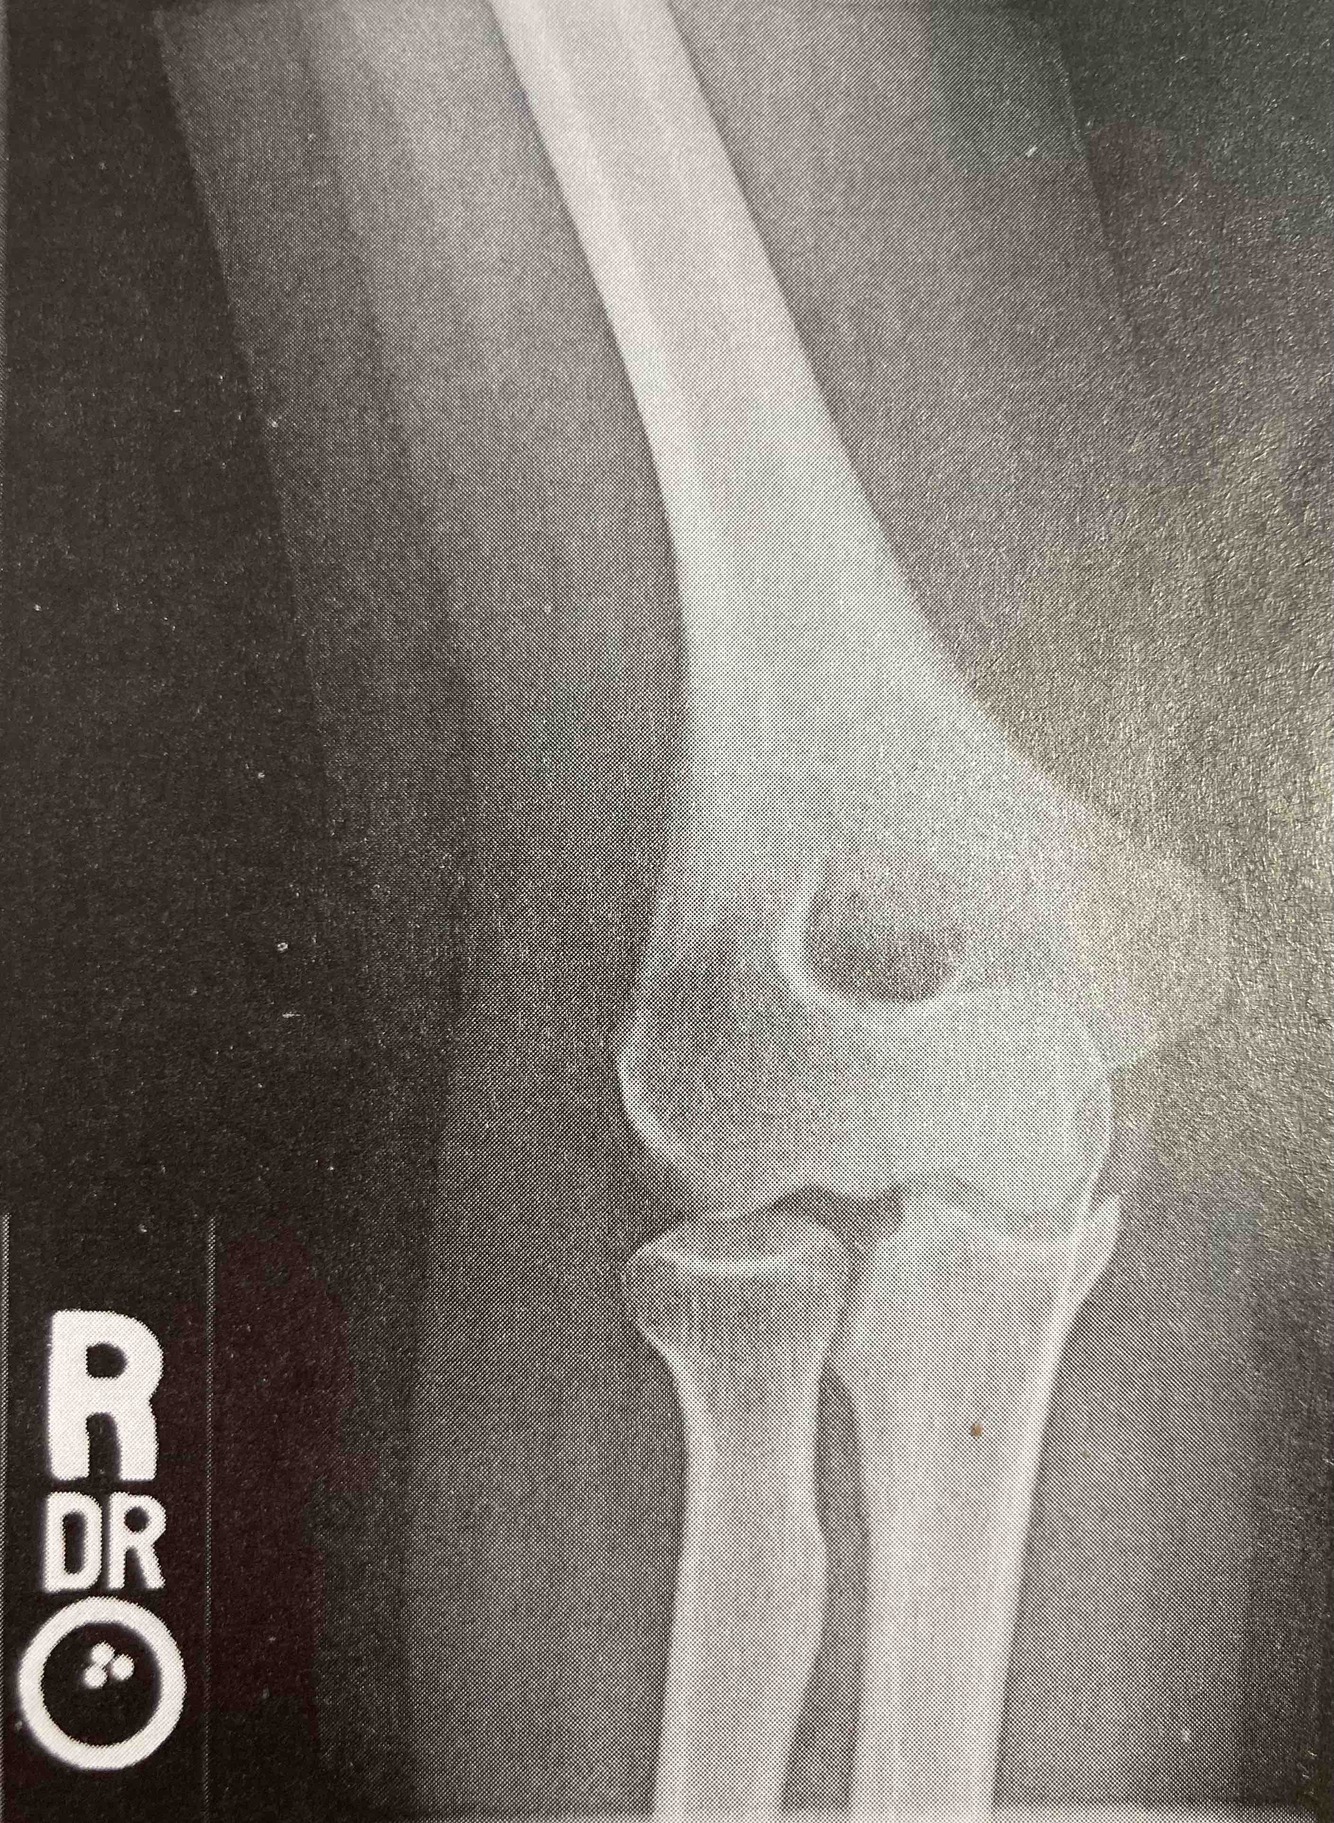

In which of the following projections was the image below made?

• AP

• Medial/internal oblique

• Lateral/external oblique

• Acute flexion

A

Lateral/external oblique